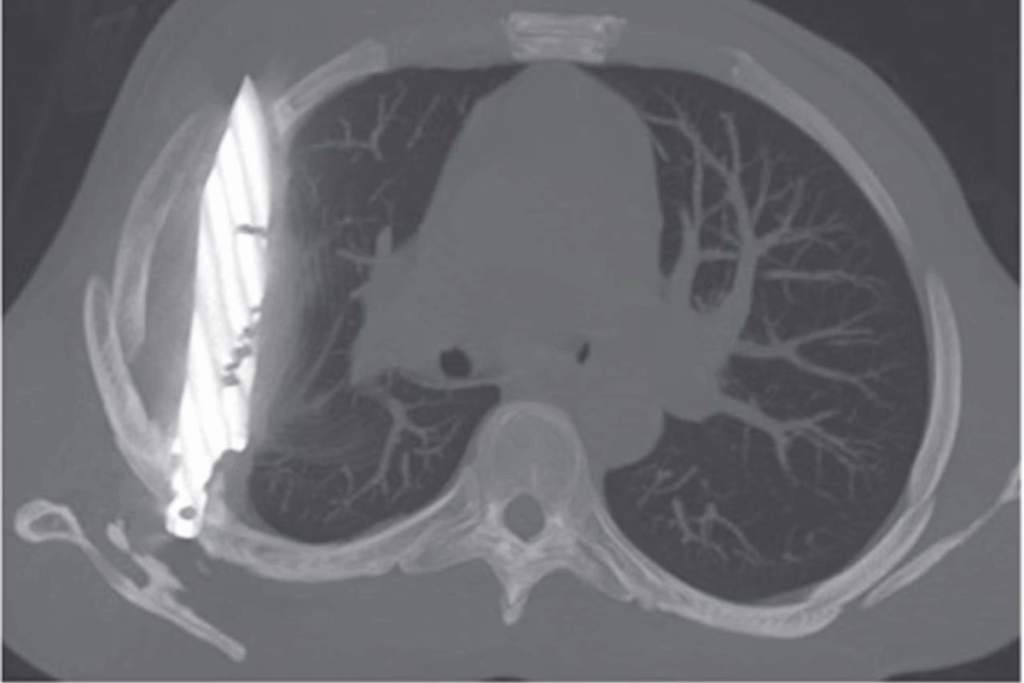

O raio-x revelou que a lâmina estava presa ao lado direito do tórax, encostada à escápula, mas não atingiu nenhum órgão vital. A secreção e o pus foram causados pela presença do corpo estranho e pelo tecido danificado ao redor. O paciente passou por uma cirurgia bem-sucedida para remover a faca e teve uma recuperação completa.